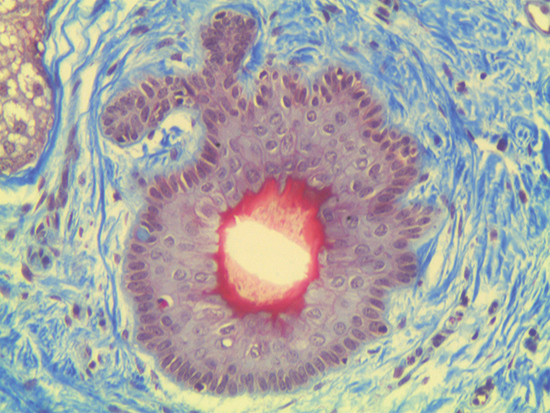

Figure 3 was captured using #59-878 20X M Plan Apo Objective. This infinity corrected objective has a numerical aperture of 0.42, field of view on a ½" sensor of 0.32mm x 0.24mm, and a resolving power of 0.7μm. Figure 3 displays the entire cell within the given field of view; the surrounding extracellular matrix is sectioned in greater detail, and the intracellular molecules are much larger and more visible than in either Figure 1 or Figure 2.

Figure 3: Trichrome Stain of Dermal Tissue Samples at 20X Magnification Using #59-878 Objective